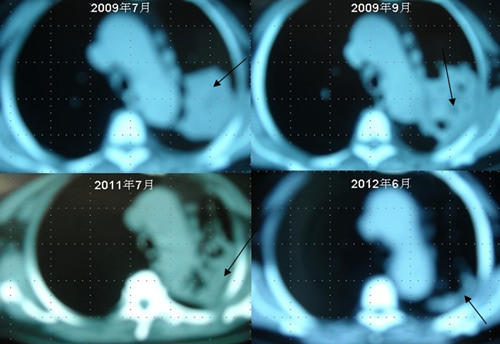

患者李某某,女,64歲,于2009年6月因咳嗽、喘憋、痰中帶血,經CT及病理等相關檢查確診為右肺上葉粘液腺癌, 縱膈淋巴結轉移, 左胸膜轉移,胸腔積液,因病情及體質的原因無法接受手術及放化療等殺傷性治療,采用"中醫調胃、強腎、止血、化巖法"先后共治療8個月,現患者已有質量的存活近3年。目前隨訪患者飲食、睡眠、體力均好,可獨立完成日常家務,如今患者已經67歲。

肺癌病人李XX采用“董氏治癌法”治療前后CT變化